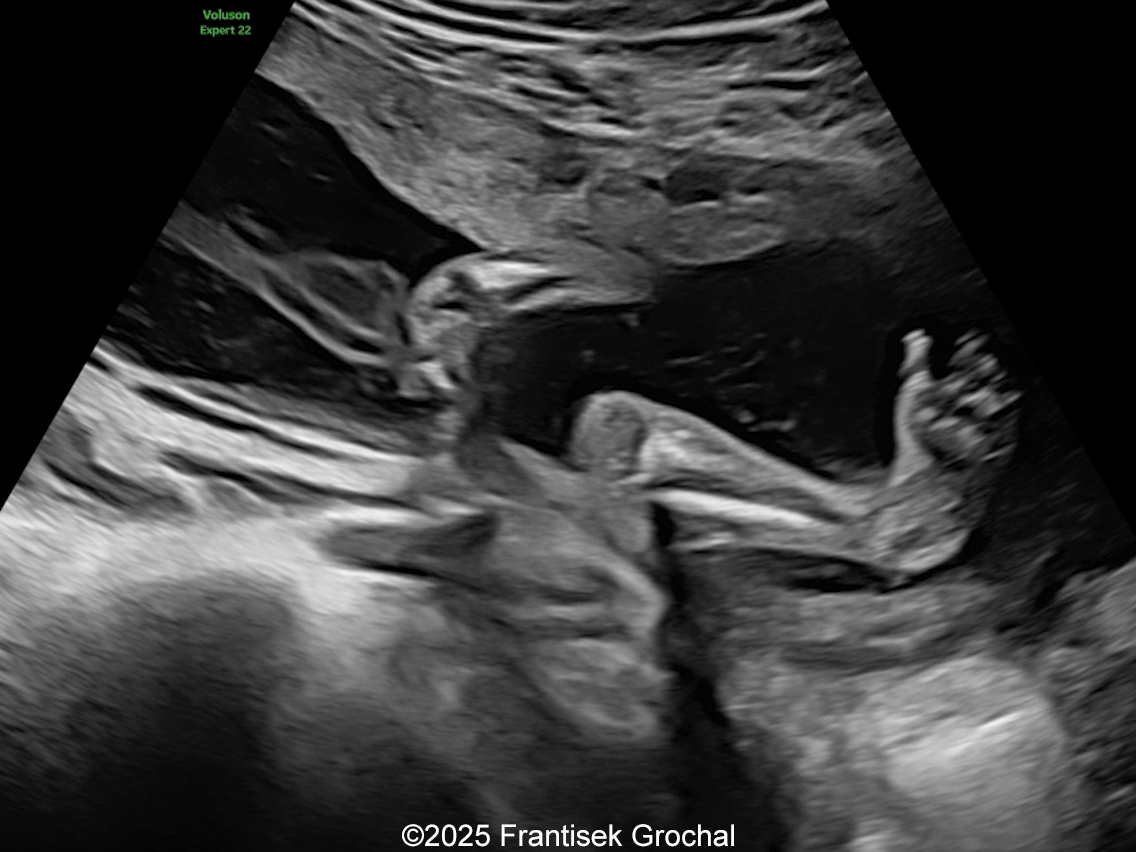

Constriction of the right thigh by the amniotic band

Image 2 Constriction of the right thigh by the amniotic band

We present a case of Amniotic Band Sequence seen in 21st week of pregnancy. The fetus showed the following findings:

• Constriction of the right thigh by the amniotic band